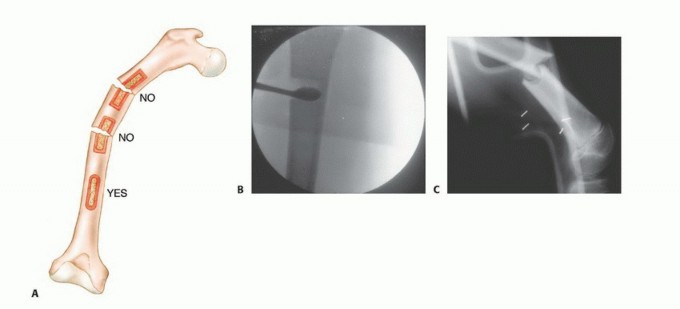

The biopsy tract itself creates an iatrogenic communication between the tumor and the external environment, effectively contaminating every anatomic layer it traverses. Because this tract must be excised en bloc with the tumor during definitive surgery, the anatomic placement of the biopsy is as critical as the resection itself. Misplacement of a biopsy tract can convert an intracompartmental lesion into an extracompartmental one, drastically altering the surgical options.

Pre Operative Planning and Patient Positioning

Preoperative planning for a musculoskeletal tumor biopsy must be as rigorous and detailed as planning for a major joint arthroplasty or complex pelvic fracture fixation. The fundamental, unbreakable rule of orthopedic oncology is that the biopsy tract must be placed in a location that allows for its complete excision en bloc with the definitive tumor specimen.

2. Trajectory: The needle trajectory must traverse the absolute minimum amount of normal tissue necessary. It must not cross multiple anatomic compartments, joint spaces, or contaminate major neurovascular bundles.

- Incision Orientation: The incision must be strictly longitudinal. Transverse incisions contaminate a wider swath of skin and subcutaneous tissue, making subsequent en bloc elliptical excision exceedingly difficult or impossible without massive soft tissue defects that require complex flap coverage.